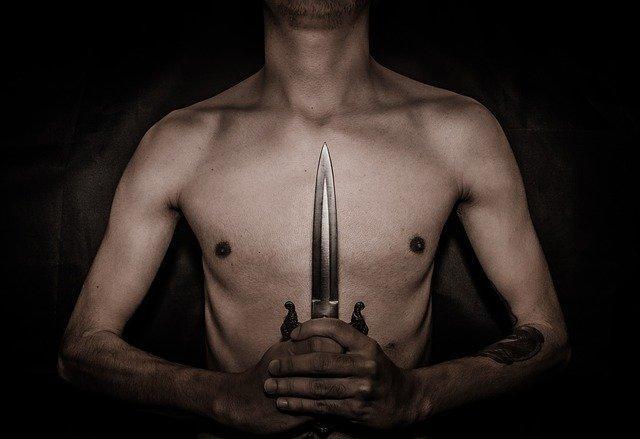

Более года 25-летний житель Филиппин проходил с крупным ножевым лезвием, застрявшим в грудной клетке совсем рядом с его легкими. Единственными побочными ощущениями от этого у него были непонятные колющие боли в холодную погоду.

Мужчина из города Кидапаван (Филиппины), который испытывал колющую боль в груди в холодную погоду, узнал, что у него в груди застряло лезвие ножа длиной четыре дюйма (около 10 см), после того, как он сделал обычный рентгеновский снимок.

25-летний Кент Райан Томао был более чем сбит с толку, когда врачи сказали ему, что в его груди, очень близко к одному из его легких, находится "предмет, напоминающий нож".

В больницу Томао попал для того, чтобы всего лишь сделать рентген грудной клетки, который был ему необходим для подачи заявления о приеме на работу в шахту в Агусан-дель-Сур, и даже представить себе не мог, что с ним что-то не так.

После того, как врачи показали ему шокирующий рентгеновский снимок с большим лезвием ножа в груди, Томао рассказал, что он не испытывал большой боли и лишь иногда у него что-то болезненно кололо в груди, как правило в холодную погоду.

Эти симптомы были столь незначительными, что Томао не думал о походе в больницу из-за них, и тем более он не думал, что это из-за того, что в его теле находится крупный инородный предмет.

"Я всегда удивляюсь, почему я чувствовал боль в груди в холодную погоду. Но я понятия не имею, что у меня в груди нож", — сказал Томао местной радиостанции.

На вопрос, знает ли он, как лезвие попало в его грудь, Кент сказал врачам, что по всей видимости это случилось из-за вооруженного нападения на него более года назад.

Якобы в июне прошлого года Томао ехал на мотоцикле, когда на него напала группа бандитов, вооруженных ножами. Они нанесли ему несколько колото-режущих ранений и Томао быстро потерял сознание.

Он очнулся уже в больнице, где его порезы, в основном неглубокие, обработали и зашили. Однако, по всей видимости, ему не делали там рентгеновского снимка и никто из врачей не узнал, что в груди Томао застряло лезвие.

Вскоре Томао был выписан из этой больницы и далее не вспоминал о нападении бандитов, а колющие ощущения в груди в холодную погоду относил к особенностям своего организма.

Сейчас Томао не держит обиды на тех врачей за то, что они пропустили нож в его груди и он даже не называл их имена, чтобы не создавать для них никаких проблем. Все, что он хочет сейчас, чтобы хирурги вытащили из него это лезвие и он смог начать работать на шахте.